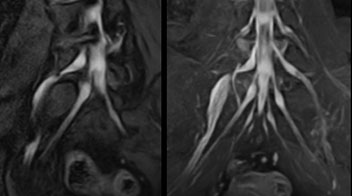

According to Tanji, methods such as ProSet FFE, STIR or 3D VISTA are anatomically nonselective because background signals, for instance from blood vessels, often interfere with nerves, which hampers evaluation of details, especially at the peripheral side of the nerves.

“For both brachial and lumbar plexus, we are currently using a 230 mm FOV and voxels of about 1 x 1 x 2 mm acquired (1 x 1 x 1 mm reconstructed). This provides us a good representation of the nerves, even though this FOV is relatively small. Regarding the inplane resolution, we hope to be able to bring that down to 0.7 mm, similar to our typical 2D multislice T2W images,” says Tanji.

Implementing NerveVIEW without lengthening exam time “The source images of NerveVIEW exhibit a contrast similar to STIR or fat-suppressed T2-weighted images. So, in our neurography exams we are replacing the 2D T2-weighted coronal sequence with 3D NerveVIEW. With this, we add a lot of useful information without adding scan time. This is important for patients with severe lower extremity symptoms, as they often find it difficult to maintain still during the whole MRI examination, so the exam should be as short as possible.” “We have currently implemented 3D NerveVIEW on our Achieva 3.0T dStream MRI system only. Because the 3D NerveVIEW method is based on a background signal suppression technique, we decided to use the high SNR of our 3.0T MRI system for obtaining the best possible visualization of peripheral nerves,” says Tanji. “Where NerveVIEW of the lumbar plexus is currently used as a subroutine scan for patients with strong lower limb symptoms, its use for visualization of the brachial plexus, is currently limited to special cases such as schwannomas and neuritis, usually only 1 or 2 cases per month.”